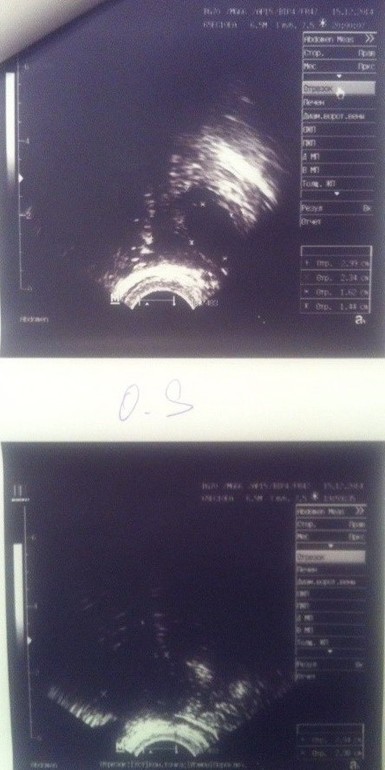

Фолликулометрия 11 ДЦ

Не понимаю как но я дошла до узи и получила консультацию врача. Прошу под кат Первое что меня приятно удивило так это то что врач ОН. Я всегда считала что мужчины лучше девушек (сори). Эндометрий ну ооочень тоненький 4 мм. ДФ в этот раз в ЛЯ 16*14, к 14-ому ДЦ должен созреть и лопнуть. Что касается моих гормонов ЛГ, ФСГ,Пролактин он сказал что очень даже все хорошо, НО если овуляция сама не произойдет будем наращивать эндометрий. Примерно так:

и конечно же мои снимки